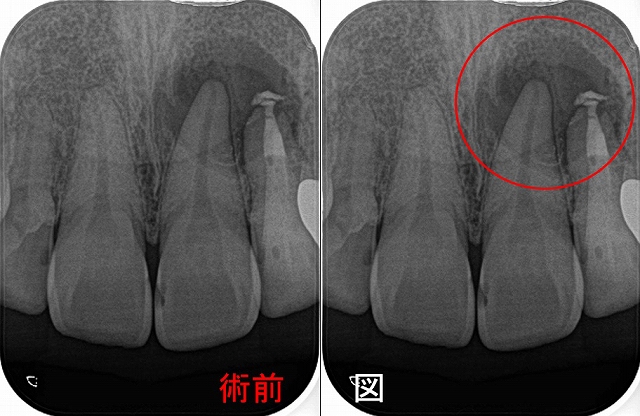

レントゲンを撮ると

はっきり根尖病変写っているんですけど・・・

過去に抜髄をしているようですが、4根管中1根(口蓋根)しか治療していない感じ

そこから、1年後

病変は殆ど無くなってきています

(他の歯科医院で治療をした際に仮歯を外したそうなんですが、縁下ににセメントが・・・)

ただ、9月から違和感というか痛みがでてきているそうで、温かい物冷たいもので痛みが出るそう。

先生も患者さんもこの歯を疑っているようなんですが・・・